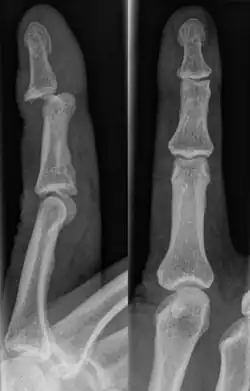

Injuries that force the finger towards the back of the hand may cause damage to the volar plate.[12] This is a ligament on the palm side of the hand that prevents hyperextension.[13] Volar plate damage may be assessed by pressing the finger bones from the back towards the palm. If either individual bone of the affected joint moves freely towards the palm, it is indicative of a tear.[2] Tears of the volar plate may lead to an avulsion fracture – when a piece of bone is pulled off with the ligament.[13] This is due to the thickness and strength of the ligament.[14] To rule out an avulsion fracture, x-rays are frequently utilized in evaluation of suspected volar plate tears.[12] Volar plate avulsions are most evident on lateral views.[2]

DIP dislocations may also involve a complete tear of the extensor digitorum tendon.[16] This tendon is part of a muscle that straightens the tip of the finger.[9] If left untreated, this may lead to permanent inability to straighten the finger at the affected DIP joint.[16] This particular type of injury is known as mallet finger. It too, is commonly associated with an avulsion fracture.[17] It is a variation of a jammed finger, where the extensor tendons on the back of the finger are damaged.[18] Mallet finger occurs in similar situations as a jammed finger. The tendon that extends the tip of the finger is torn due to trauma causing it to flex beyond normal range.[17] It is characterized by a difficulty extending the finger or opening the hand.[19] Symptoms common to jammed fingers are likely, though a painless mallet finger is not uncommon.[2]

Fractures

Fractures are instances where the bone's structural integrity has been compromised.[20] If a jammed finger produces a fracture, pain will be greatest at the bone as opposed to the joint.[2] There may also be visual deformation of the bone itself.[6] As with any skeletal injury, an x-ray can be conducted to verify the presence of a fracture.[1] The distal phalanx is especially vulnerable to avulsion fractures.[1] These avulsion fractures are common following a first time dislocation of the DIP.[1]